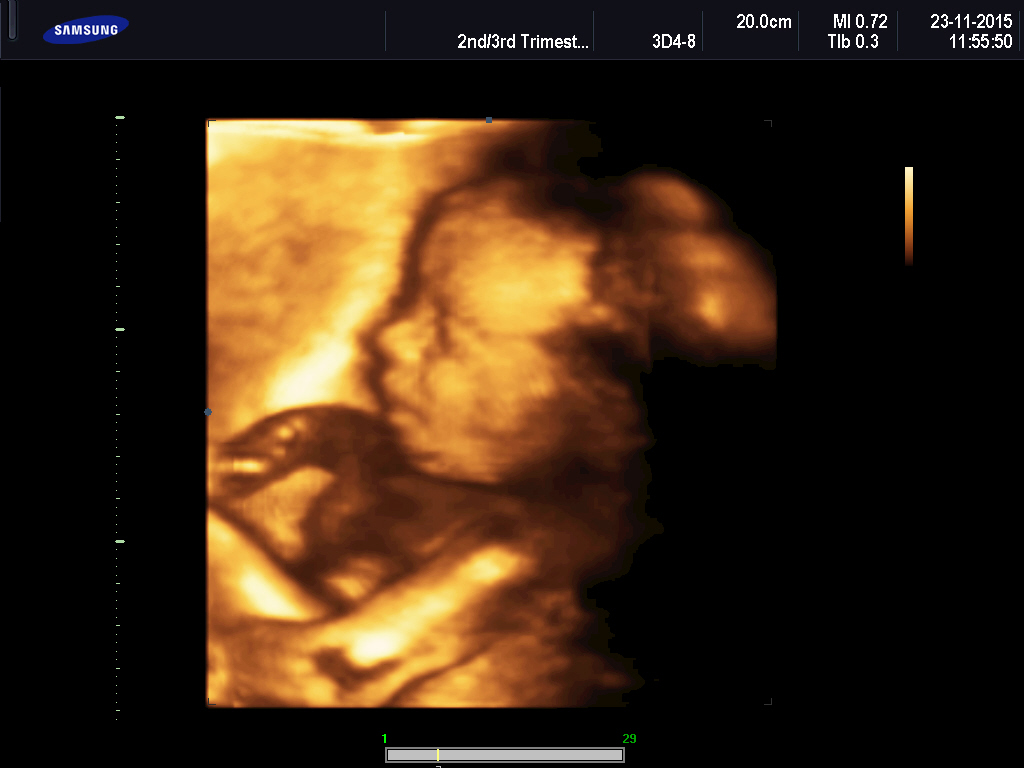

@briketaaaa krásná fotecka😊

@briketaaaa krásna foto 🙂..,gratuluji už ted je nádherný 😉

@briketaaaa Ten je krásný😊vypada moooc spokojene,nam udelaji 4D az po 20tt u dvojčátek😊